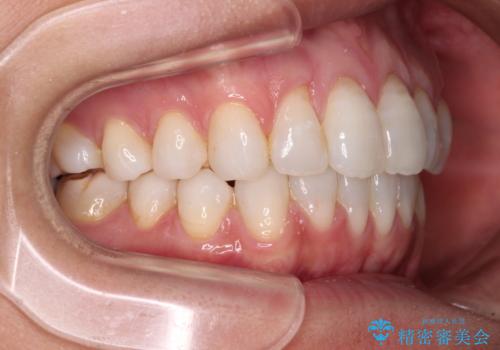

少しだけ飛び出た前歯を整えたい インビザラインによる矯正治療

- 少しだけ前に飛び出ている前歯を気にして来院された患者様です。

上顎歯列全体を後方に移動させる必要があり、インビザライン単体での治療は困難と判断し、補助装置により左右側方歯列を移動させた後にインビザラインを用いることとしました。